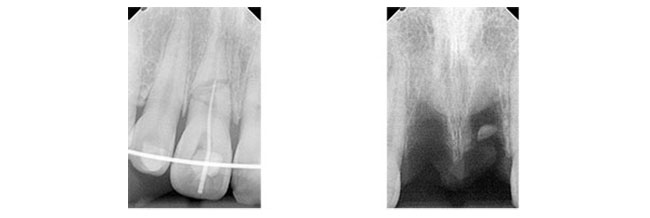

з—ҮдҫӢпј‘

еӨ–еӮ·гҒ«гӮҲгӮҠжӯҜеҶ дҝ®еҫ©еҫҢгҖҖзҹҜжӯЈз”ЁгғҜгӮӨгғӨгғјгҒ«гҒҰеӣәе®ҡ

гҒқгҒ®еҫҢгҖҖжӯҜж №з ҙжҠҳгӮ’иө·гҒ“гҒ—з–јз—ӣгӮ’зҷәз”ҹгҒ—гҒҹгҒҹгӮҒгӮ„гӮҖгҒӘгҒҸжҠңжӯҜгҖӮ

гҒ•гӮүгҒ«гҒқгҒ®еҫҢгҖҖгӮӨгғігғ—гғ©гғігғҲгҒ«гӮҲгӮҠдҝ®еҫ©гҒ—гҒҹз—ҮдҫӢ

иҮӘи»ўи»ҠгҒ§гҒ®дәӨйҖҡдәӢж•…гҒ«гӮҲгӮҠеүҚжӯҜжү“ж’ІгҖҒз ҙжҠҳ

жӯҜеҶ дҝ®еҫ©

е·ҰдёҠпј‘з•ӘжӯҜеҶ дҝ®еҫ©еҫҢгҖҖеӣәе®ҡ

еӣәе®ҡеҫҢжӯҜж №з ҙжҠҳгҒ«гӮҲгӮҠз—ӣгҒҝгҒҢгҒ§гҒҰгҒҚгҒҹгҒ®гҒ§гҒ”жң¬дәәж§ҳгҒ«дәҶи§ЈгӮ’гҒЁгӮҠ

гӮ„гӮҖгҒӘгҒҸжҠңжӯҜгҒ—гҒҹгҖӮгҒқгҒ®еҫҢгҖҖгӮӨгғігғ—гғ©гғігғҲжІ»зҷӮгҒ«гӮҲгӮҠдҝ®еҫ©гҒ—гҒҹгҖӮ

иЎ“еҫҢ

| в‘ жІ»зҷӮеҗҚ | дәӨйҖҡдәӢж•…гҒ«гӮҲгӮӢеүҚжӯҜз ҙжҠҳгҖӮгӮӨгғігғ—гғ©гғігғҲгҒ«гӮҲгӮӢдҝ®еҫ© |

|---|---|

| в‘ЎиІ»з”Ё | гӮёгғ«гӮігғӢгӮўгҒ«гӮҲгӮӢеүҚжӯҜдҝ®еҫ©пјҲгӮөгғјгӮёгӮ«гғ«гӮ¬гӮӨгғүдҪҝз”Ёз—ҮдҫӢпјүпј“пјҗдёҮеҶҶпјҸжң¬ |

| в‘ўжңҹй–“ | пј“жңҲпј‘пјҳж—ҘжҠңжӯҜгҖҒпј–жңҲпј‘пјҷж—ҘгӮӘгғҡгҖҒпјҷжңҲпј’пјҳж—ҘTEKгӮ»гғғгғҲгҖҒпј‘пјҗжңҲпј‘пј‘ж—ҘгӮёгғ«гӮігғӢгӮўгӮ»гғғгғҲгҖҖе®ҢдәҶгҒҫгҒ§зҙ„пј—гҒӢжңҲ |

| в‘ЈйҖҡйҷўй »еәҰ | гӮӘгғҡеҫҢгҒҜзҝҢж—Ҙжҙ—жө„гҖҒпј‘йҖұй–“еҫҢиҰіеҜҹгҖҒгҒ•гӮүгҒ«пј‘йҖұй–“еҫҢжҡ«й–“зҫ©жӯҜгҒ®зўәиӘҚгҖҒиӘҝж•ҙгҖҒпј‘гҒӢжңҲеҫҢзўәиӘҚгҖҒжё…жҺғгҖҒгҒӮгҒЁпј‘гҒӢжңҲгҒ”гҒЁгҒ«зўәиӘҚгҖҒпјҷжңҲгҒ«PTVгҒ«гҒҰгӮӘгӮ№гғҶгӮӘгӮӨгғігғҶгӮ°гғ¬гғјгӮ·гғ§гғігҒ®зўәиӘҚгҖҒеҚ°иұЎгҖҒTEKиЈ…зқҖгҖҒзҙ„пј’йҖұй–“еҫҢгҖҖгӮёгғ«гӮігғӢгӮўгӮ»гғғгғҲ |

| в‘ӨжӮЈиҖ… | пј’пјҗд»ЈгҖҖеҘіжҖ§ |

| в‘ҘжІ»зҷӮеҶ…е®№ | иҮӘи»ўи»ҠгҒЁи»ҠгҒ®дәӨйҖҡдәӢж•…гҒ§еүҚжӯҜгӮ’жү“ж’ІгҖҒи…«и„№гҖӮжҡ«й–“еӣәе®ҡгҒ§еӣәе®ҡгҒ§гҒҚгӮӢгҒҢжӯҜж №з ҙжҠҳгҒ®гҒҹгӮҒж №з®ЎжІ»зҷӮгӮ’гҒҠгҒ“гҒӘгҒЈгҒҹгҒҢз ҙжҠҳз·ҡгҒҢеәғгҒҢгӮҠжҠңжӯҜгӮ’дҪҷе„ҖгҒӘгҒҸгҒ•гӮҢгҒҹгҖӮиӢҘгҒ„еҘіжҖ§гҒ§гҒӢгҒӨеүҚжӯҜпј’жң¬гҒ®гҒҹгӮҒгӮёгғ«гӮігғӢгӮўдҝ®еҫ©гӮ’гҒҷгӮӢгҒ“гҒЁгҒ«гҒӘгҒЈгҒҹгҖӮ |

| в‘ҰжІ»зҷӮзөҗжһң | еҜ©зҫҺзҡ„гҒ«гӮӮж©ҹиғҪзҡ„гҒ«гӮӮжӮЈиҖ…гҒ•гӮ“гҒ”жң¬дәәгҒҢжәҖи¶ігҒ§гҒҚгӮӢзөҗжһңгҒЁгҒӘгҒЈгҒҰгҒҠгӮҠе®ҡжңҹжӨңиЁәгӮ’гҒҠйЎҳгҒ„гҒ—гҒҰгҒ„гӮӢгҖӮ |

| ⑧注ж„ҸзӮ№ | еүҚжӯҜгҒ®гҒҹгӮҒеҜ©зҫҺзҡ„гҒ«гӮӮж©ҹиғҪзҡ„гҒ«гӮӮеӣ°гӮүгҒӘгҒ„гӮҲгҒҶгҒ«гӮөгғјгӮёгӮ«гғ«гӮ¬гӮӨгғүгӮ’дҪҝз”ЁгҒ—гҒҹгҖӮгҒ“гӮҢгҒ«гӮҲгӮҠиЎ“еүҚгҒ«жӮЈиҖ…гҒ•гӮ“гҒ«дәҲжё¬гӮ’иҰӢгҒҰгҒ„гҒҹгҒ гҒҸгҒ“гҒЁгҒҢгҒ§гҒҚе®үеҝғгҒ«гӮӮгҒӨгҒӘгҒҢгҒЈгҒҹгҒЁиҖғгҒҲгҒҰгҒ„гӮӢгҖӮгҒ„гҒҫгҒ®гҒЁгҒ“гӮҚеӨ§дёҲеӨ«гҒ§гҒҷгҒҢгӮ№гӮ№гӮҜгғӘгғҘгғјеӣәе®ҡгҒ®зӮәдёҮгҒҢдёҖиў«гҒӣгҒ®гӮёгғ«гӮігғӢгӮўгҒ«гғҲгғ©гғ–гғ«гҒҢзҷәз”ҹгҒ—гҒҰгӮӮдҝ®зҗҶгҒҷгӮӢгҒ«гҒҜжҜ”ијғзҡ„е®№жҳ“гҒЁжҖқгӮҸгӮҢгӮӢгҖӮ |